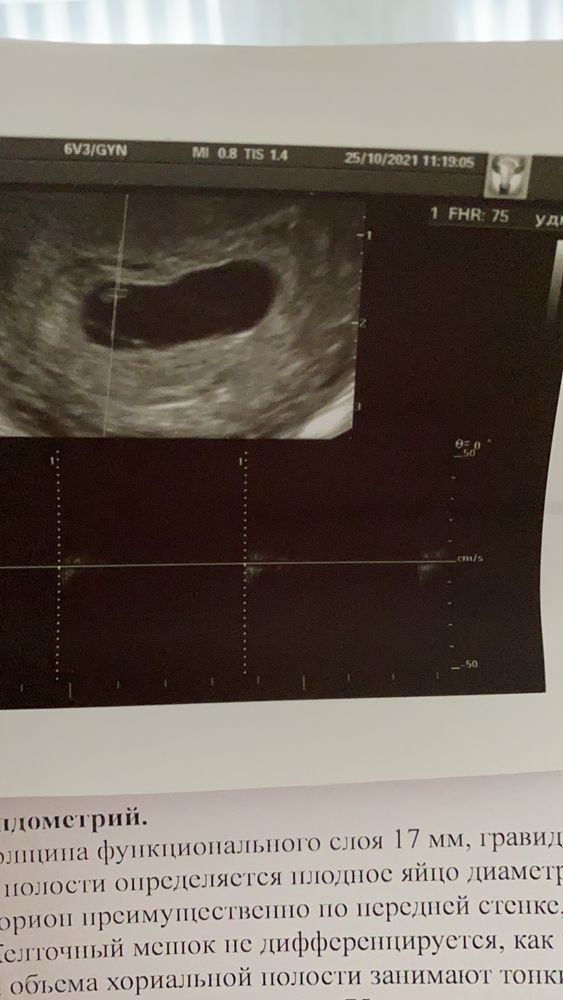

По мес 6,6 дней. Сначала не увидели эмбрион, в конце все таки уловили ктр 3 мм, сердцебиение 75 ударов( что соответствует началу 6 недели, у меня почти 7)желточного мешка нет и опять какие то тяжи в плодном яйца как и в прошлый раз. Ещё и гематома. Ничего не понимаю 🤦🏻♀️ неужели опять неудача. Ждём неделю переделаю у другого специалиста.